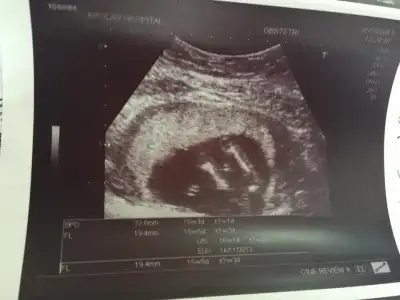

sonra geçtik ultrasonumuza paşam sereserpe yatıyodu bi fazlalık görüyorum dedi pipsi

evirdi çevirdi her yönden gösterdiii boyu 15 cm kg si 142 grm olmuş paşamınnn herşey çok güzel Allahıma şükür

kocaman yanakları kocaman göbüşü olmuş paşamızın babasıyla göbek yarıştırıcak anlaşılannn